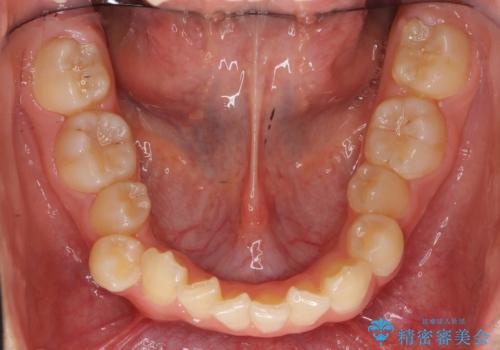

その後、右下の小臼歯を1本抜歯し、ワイヤー矯正を行いました。

犬歯の代わりに小臼歯を配列し、最小限の抜歯の本数としました。

犬歯の両側の歯に関しては移動することにより歯槽骨が順調に回復し、上顎洞底の形態にかかわらず歯根のパラレリングを行うことができました。

犬歯の両側の歯に関しては移動することにより歯槽骨が順調に回復し、上顎洞底の形態にかかわらず歯根のパラレリングを行うことができた理由としては、年齢が10代前半と若かったからだと思います。